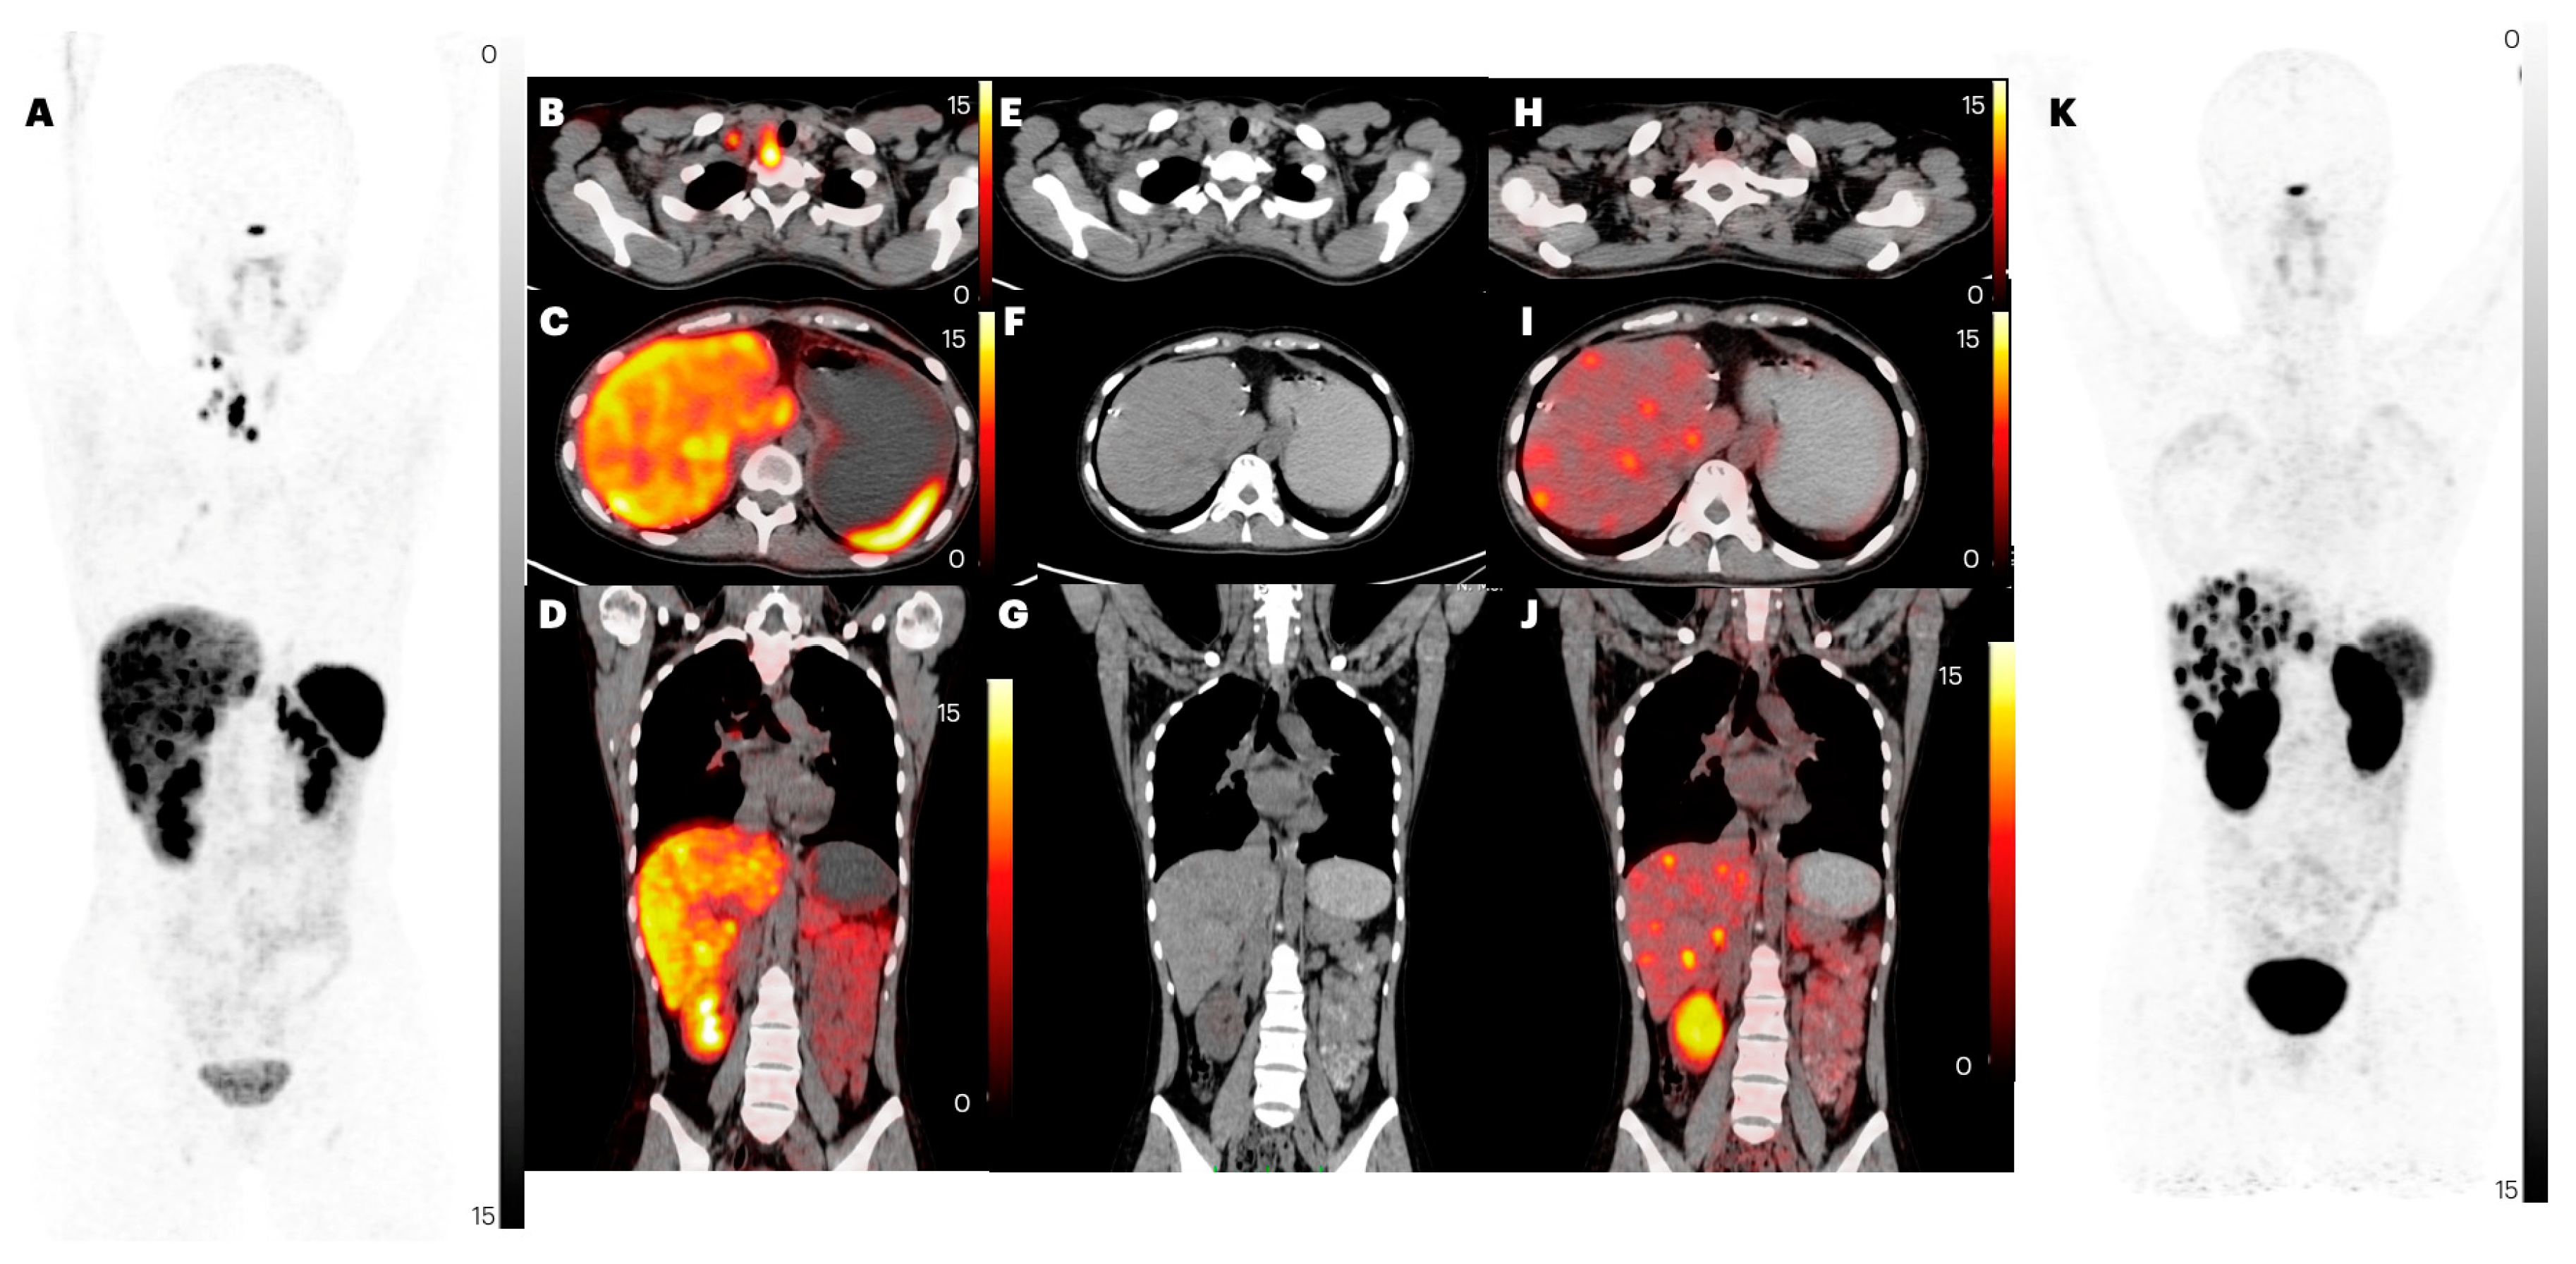

2.2.4. Liver Metastases

2.2. Comparison of Lesion Detection and Uptake between [68Ga]Ga-DOTANOC and [68Ga]Ga-DATA5m-LM4